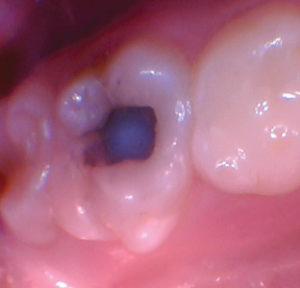

Figura 2. La exposición pulpar se produjo al excavar la dentina infectada (la exposición pulpar no se capturó en la foto). |

Figura 3. Después de quitar el techo de la cámara pulpar. |

Figura 4. Después de excavar el tejido pulpar en los orificios del canal, se utilizó una prenda de algodón seco para evaluar la salud de la pulpa mediante la aplicación de hemostasia por presión. |